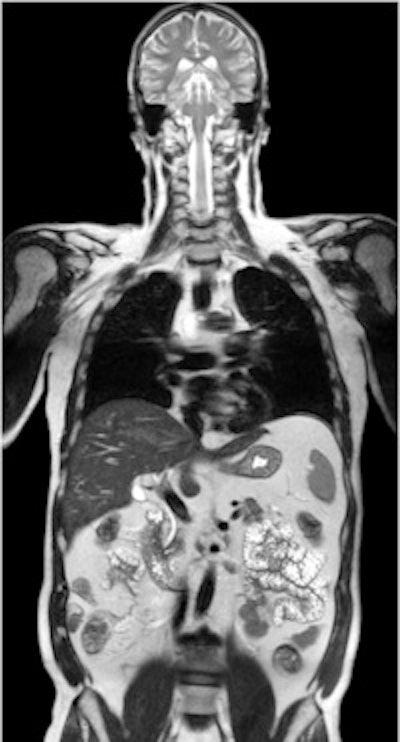

Two-station torso imaging with multitransmit. Image courtesy of Philips.